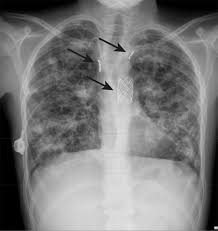

Cystic Fibrosis Lung - Cystic Fibrosis Wikipedia : Cystic fibrosis (cf) is a multisystem disorder caused by pathogenic mutations of thecftrgene (cf transmembrane conductance regulator).. Over time, cystic fibrosis can damage lung tissue so badly that it no longer works. Unique to cystic fibrosis, seen in 20% of patients; In reality, cf affects many parts of the body. Learn about cystic fibrosis, a genetic disorder that affects the lungs, pancreas, and other organs, and how to treat and live with this chronic disease. Cystic fibrosis (cf) is a chronic, progressive, and frequently fatal genetic (inherited) dis­ ease of the lung disease is the usual cause of death in most patients.

Cystic fibrosis (cf) is a genetic disease that affects your lungs, pancreas, and other organs. Over time, cystic fibrosis can damage lung tissue so badly that it no longer works. Cystic fibrosis is often thought of as a 'lung disease' owing to a collection of respiratory symptoms that manifest in people with the condition. Cystic fibrosis is an inherited condition that causes sticky mucus to build up in the lungs and digestive system. The body produces thick and sticky mucus that can clog the lungs and obstruct the pancreas. Symptoms of cystic fibrosis depend on which organs are affected and the severity of the condition. Learn about the diagnosis, symptoms, signs, treatment and prognosis for this genetic disease. Cystic fibrosis | care guidelines for nutrition management. Cystic fibrosis title pulmonary lung. Pseudomonas aeruginosa chromosomal betalactamase in patients with cystic fibrosis and chronic lung infection. Cystic fibrosis is a hereditary disease that affects the lungs and digestive system. The disease starts to express itself by changing the structure of lung tissue leading to structural. Cystic fibrosis (cf) is a multisystem disorder caused by pathogenic mutations of thecftrgene (cf transmembrane conductance regulator).

Cystic fibrosis (cf) is a chronic, progressive, and frequently fatal genetic (inherited) dis­ ease of the lung disease is the usual cause of death in most patients. Cystic fibrosis is an autosomal recessive disorder, and most carriers of the gene are asymptomatic. This causes lung infections and problems with digesting food. Cystic fibrosis is carried as an autosomal recessive trait by about 3% of the white population. Explore symptoms, inheritance, genetics of this condition. At least once a year in cf patients. Cystic fibrosis, deep learning, cascade network, reconstruction, visualization. The most serious and common complications of cystic fibrosis are problems with the lungs, also. Pseudomonas aeruginosa chromosomal betalactamase in patients with cystic fibrosis and chronic lung infection. In reality, cf affects many parts of the body. Cystic fibrosis is a hereditary disease that affects the lungs and digestive system. The disease starts to express itself by changing the structure of lung tissue leading to structural. What causes cystic fibrosis and how is cystic fibrosis inherited?